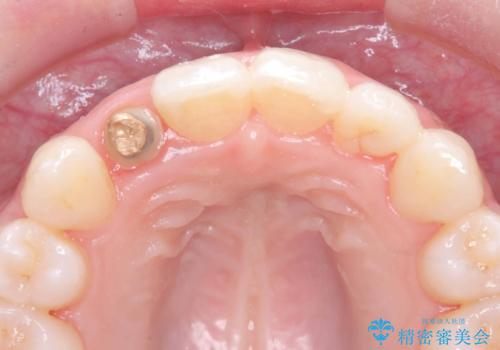

被せ物と歯の境の位置が歯肉の上に設定されており、それによって審美障害が起きていました。

歯と被せ物の境を歯肉縁下0.5㎜に設定して形成を行いオールセラミッククラウン(スペシャル)で治療を行いました。